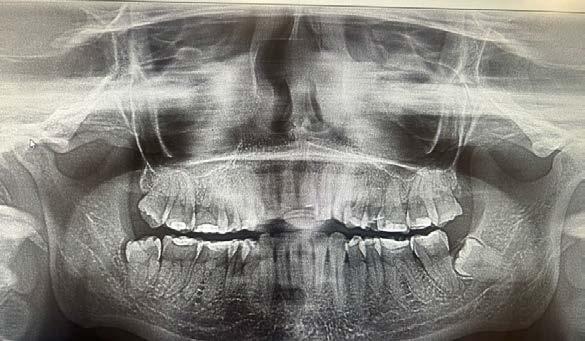

realizó una resonancia magnética de cráneo, que no mostró evidencia de actividad tumoral (Figura 1).

En 2025, la paciente presentó cefalea que posteriormente se localizó en la región maxilar. En consulta externa se realizó la exodoncia del órgano dentario 17 (Figura 2). Debido a la persistencia del dolor y la aparición de una lesión en la tuberosidad maxilar, se llevó a cabo una biopsia, cuyo resultado histopatológico fue compatible con metástasis de carcinoma ductal. Se documentó una lesión sólida de 21 mm que comprometía el hueso maxilar superior derecho, con destrucción ósea e impronta en el seno maxilar. Además, se observó compromiso del espacio graso retromaxilar, así como adoncia del segundo y tercer molar superiores derechos y ganglio submandibular derecho de 11 mm, con características sugestivas de infiltración tumoral (Figura 3).

La evaluación imagenológica mediante tomografía de maxilar y radiografía panorámica mostró una lesión lítica en el lado derecho (Figura 4). Presenta datos de recurrencia de la enfermedad a nivel sistémico en hígado, hueso y pulmón. Ante estos hallazgos, el servicio de mama decidió iniciar tratamiento radioterapéutico dirigido a la región pterigopalatina derecha, administrando una dosis total de 20 g y en 5 fracciones.